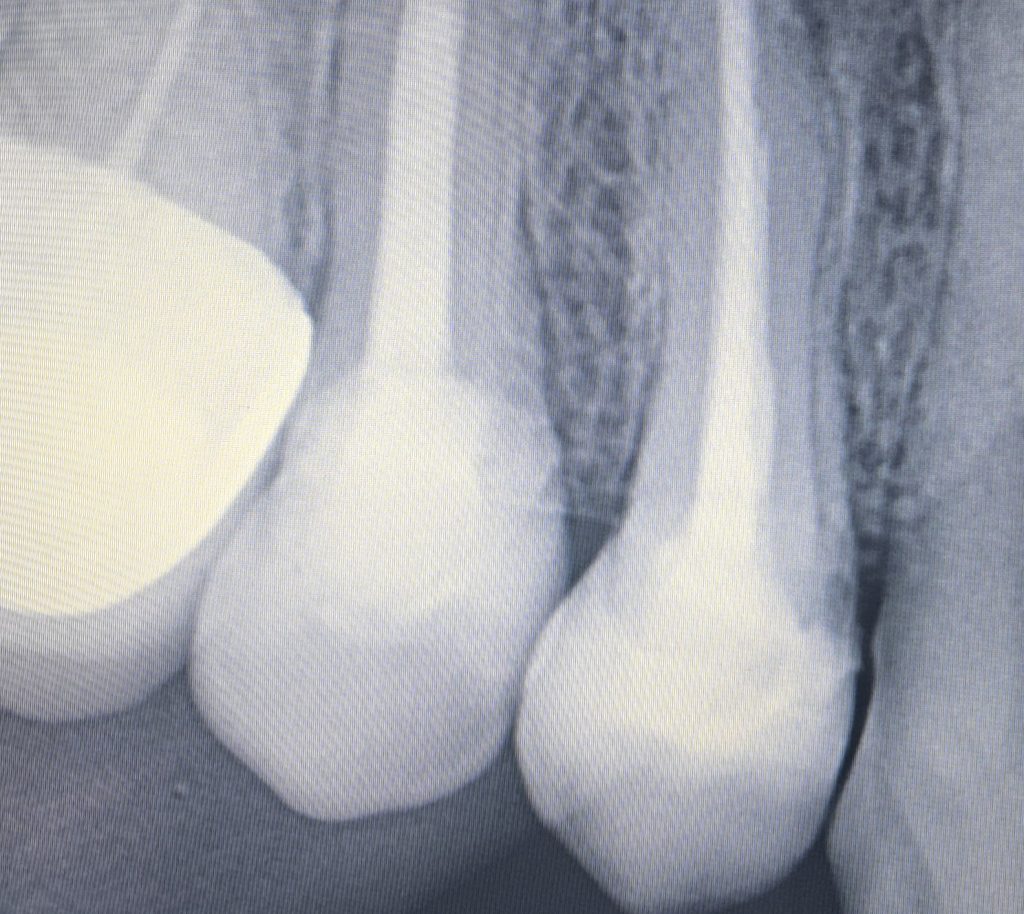

Upper right first and second premolars

Were badly decayed

Upon examination